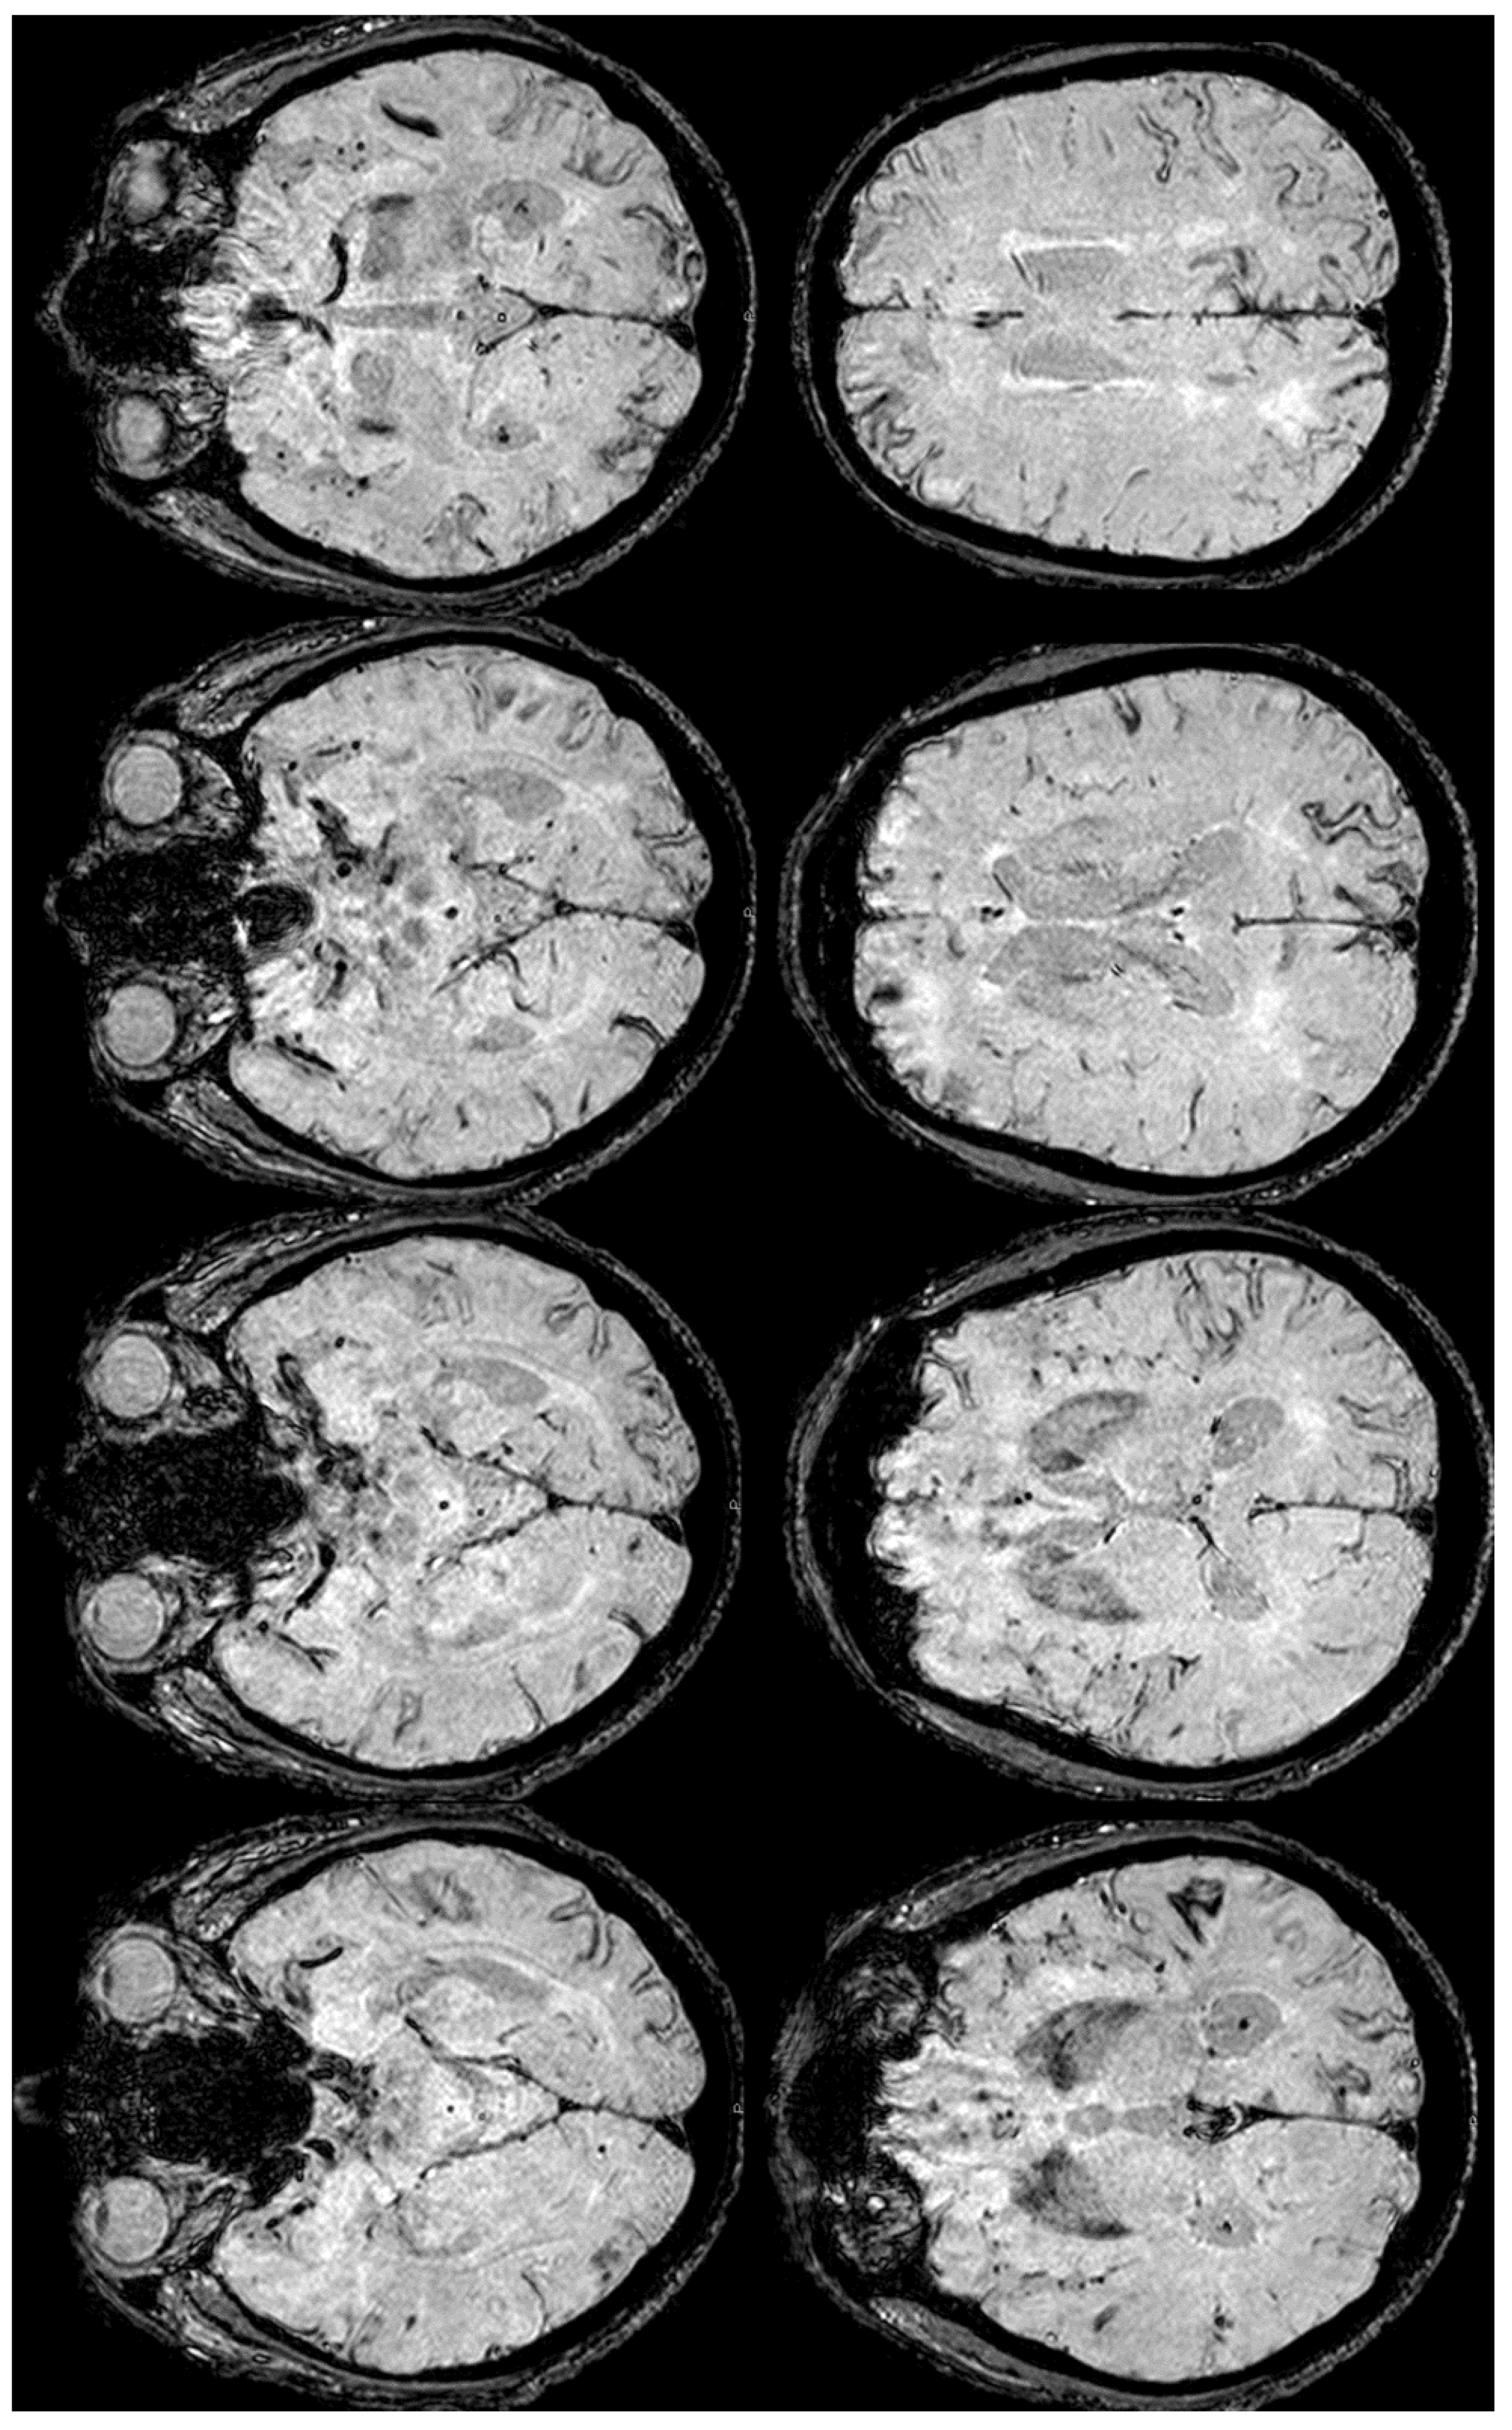

5. February 2017: First Recurrent CAA-Related Inflammation

6. December 2017: Recurrent SAH

7. April 2018: Second Recurrent CAA-Related Inflammation

8. April 2018: Third Recurrent CAA-Related Inflammation